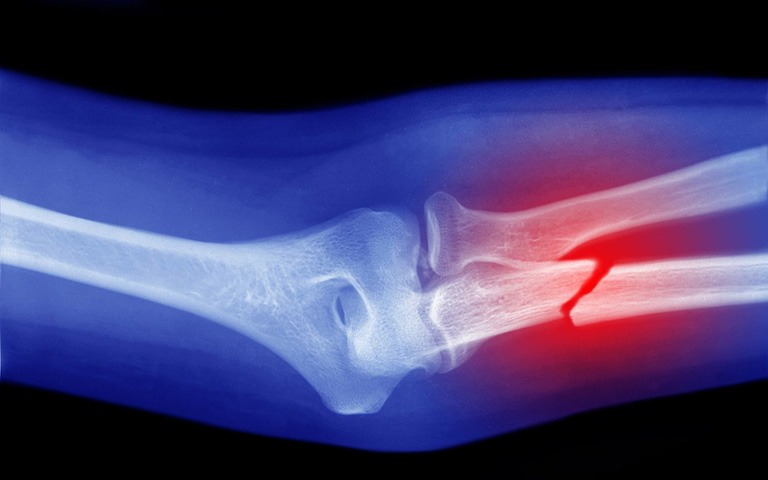

Hướng Dẫn Sơ Cứu Gãy Xương Đúng Cách

Gãy xương đòi hỏi thời gian phục hồi lâu dài. Sơ cứu đúng cách và kịp thời là quyết định quan trọng để quá trình điều trị hiệu quả hơn.

Gãy xương là tình trạng xương mất đi tính liên tục, thường là do tác động của một lực vào xương gây ra, có thể là trực tiếp hoặc gián tiếp.

Vết thương gãy xương được chia làm 2 loại chính: gãy xương kín và gãy xương hở.

Gãy xương kín: là loại tổn thương chỉ xảy ra ở xương, trong khi các tổ chức da xung quanh ổ gãy vẫn bình thường hoặc dù có tổn thương nhưng không thông với ổ gãy.

Gãy xương hở: là khi xuất hiện tổn thương ở cả bề mặt da thông với ổ gãy xương hoặc đầu xương chòi ra ngoài. Gãy xương hở rất nghiêm trọng vì nó không những gây chảy máu mà còn có nguy cơ bị nhiễm trùng nặng nề.